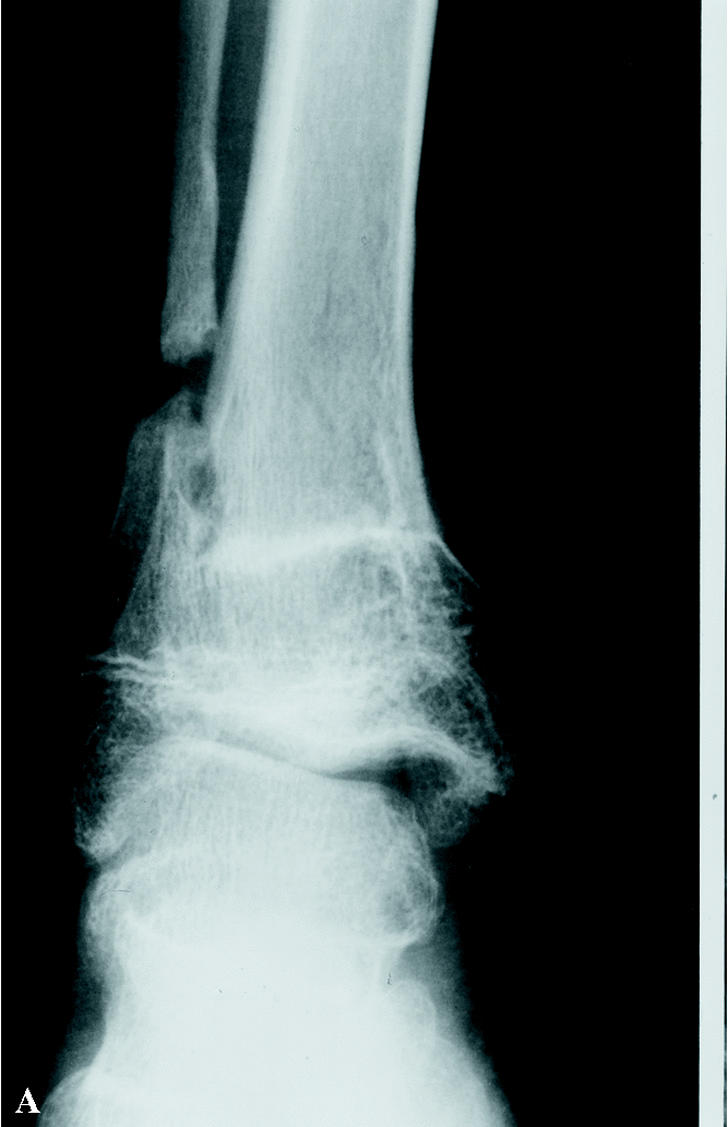

Cuando acudió a nuestras consultas presentaba un valgo de tobillo derecho y una discreta cojera por dismetría de miembros inferiores (el miembro inferior derecho es 19 mm más corto). Clínicamente estaba asintomático. En la radiografía simple se observó un valgo de la articulación tibio-peroneo-astragalina de 18°, así como la pseudoartrosis del peroné (Fig. 2). Se decidió intervenir quirúrgicamente, mediante técnica de Langenskiöld, tras retirada del tornillo del maleolo medial: se resecó el tejido fibroso y se refrescó el extremo proximal; se realizó una osteotomía en el tercio inferior de la tibia, con extracción de una cuña interna para lograr un efecto de varización, sintetizándola con tres agujas de Kirschner introducidas desde el maleolo interno y, por último, se procedió a cruentar la cara externa de la metáfisis distal tibial y la cara interna de la metáfisis distal del peroné con aporte de injerto óseo. Se inmovilizó con férula de yeso. En el mismo acto quirúrgico se realizó epifisiodesis proximal percutánea de la tibia izquierda, para igualar la longitud de ambos miembros, dado que a la dismetría existente se añadía la cuña extraída de tibia derecha. A las seis semanas, tras observar en las radiografías formación de callo, se retiraron las agujas y se inició la carga. Tres meses tras la cirugía se apreció la consolidación radiológica tibio-peronea, con alineación correcta del tobillo (Fig. 3), clínicamente sin síntomas y con una movilidad normal.

Figura 3. Imágenes antero-posterior (A) y lateral (B) una vez fusionadas las metáfisis distales de tibia y peroné.